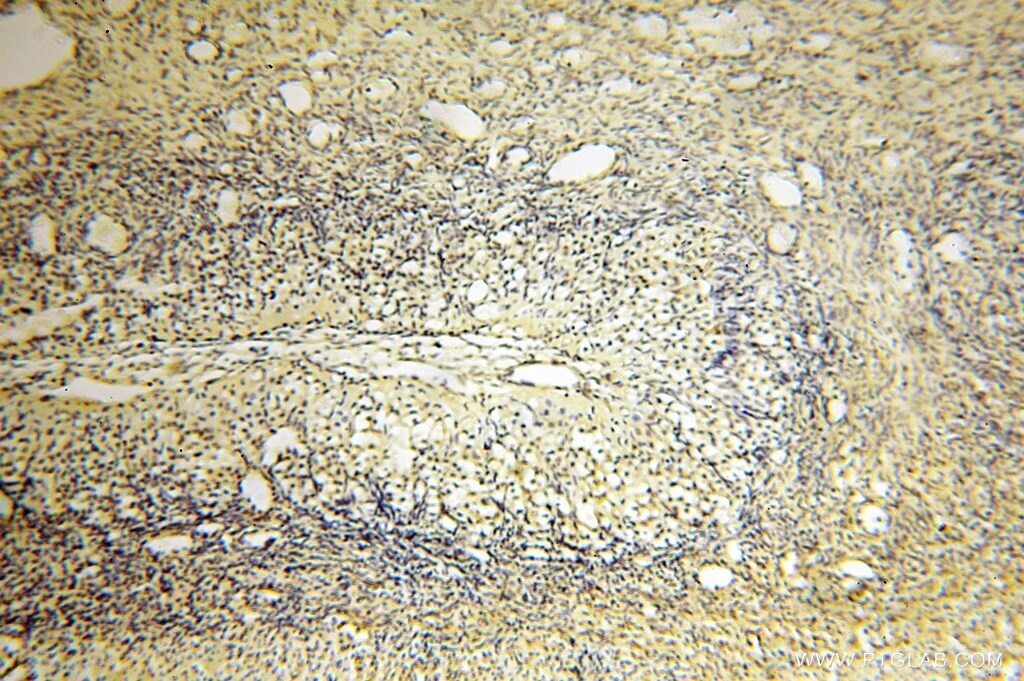

- Submitted by

- Invitrogen Antibodies (provider)

- Main image

- Experimental details

- Immunohistochemistry of paraffin-embedded human testis using 16762-1-AP (AGPAT6 antibody) at dilution of 1:100 (under 10x lens).